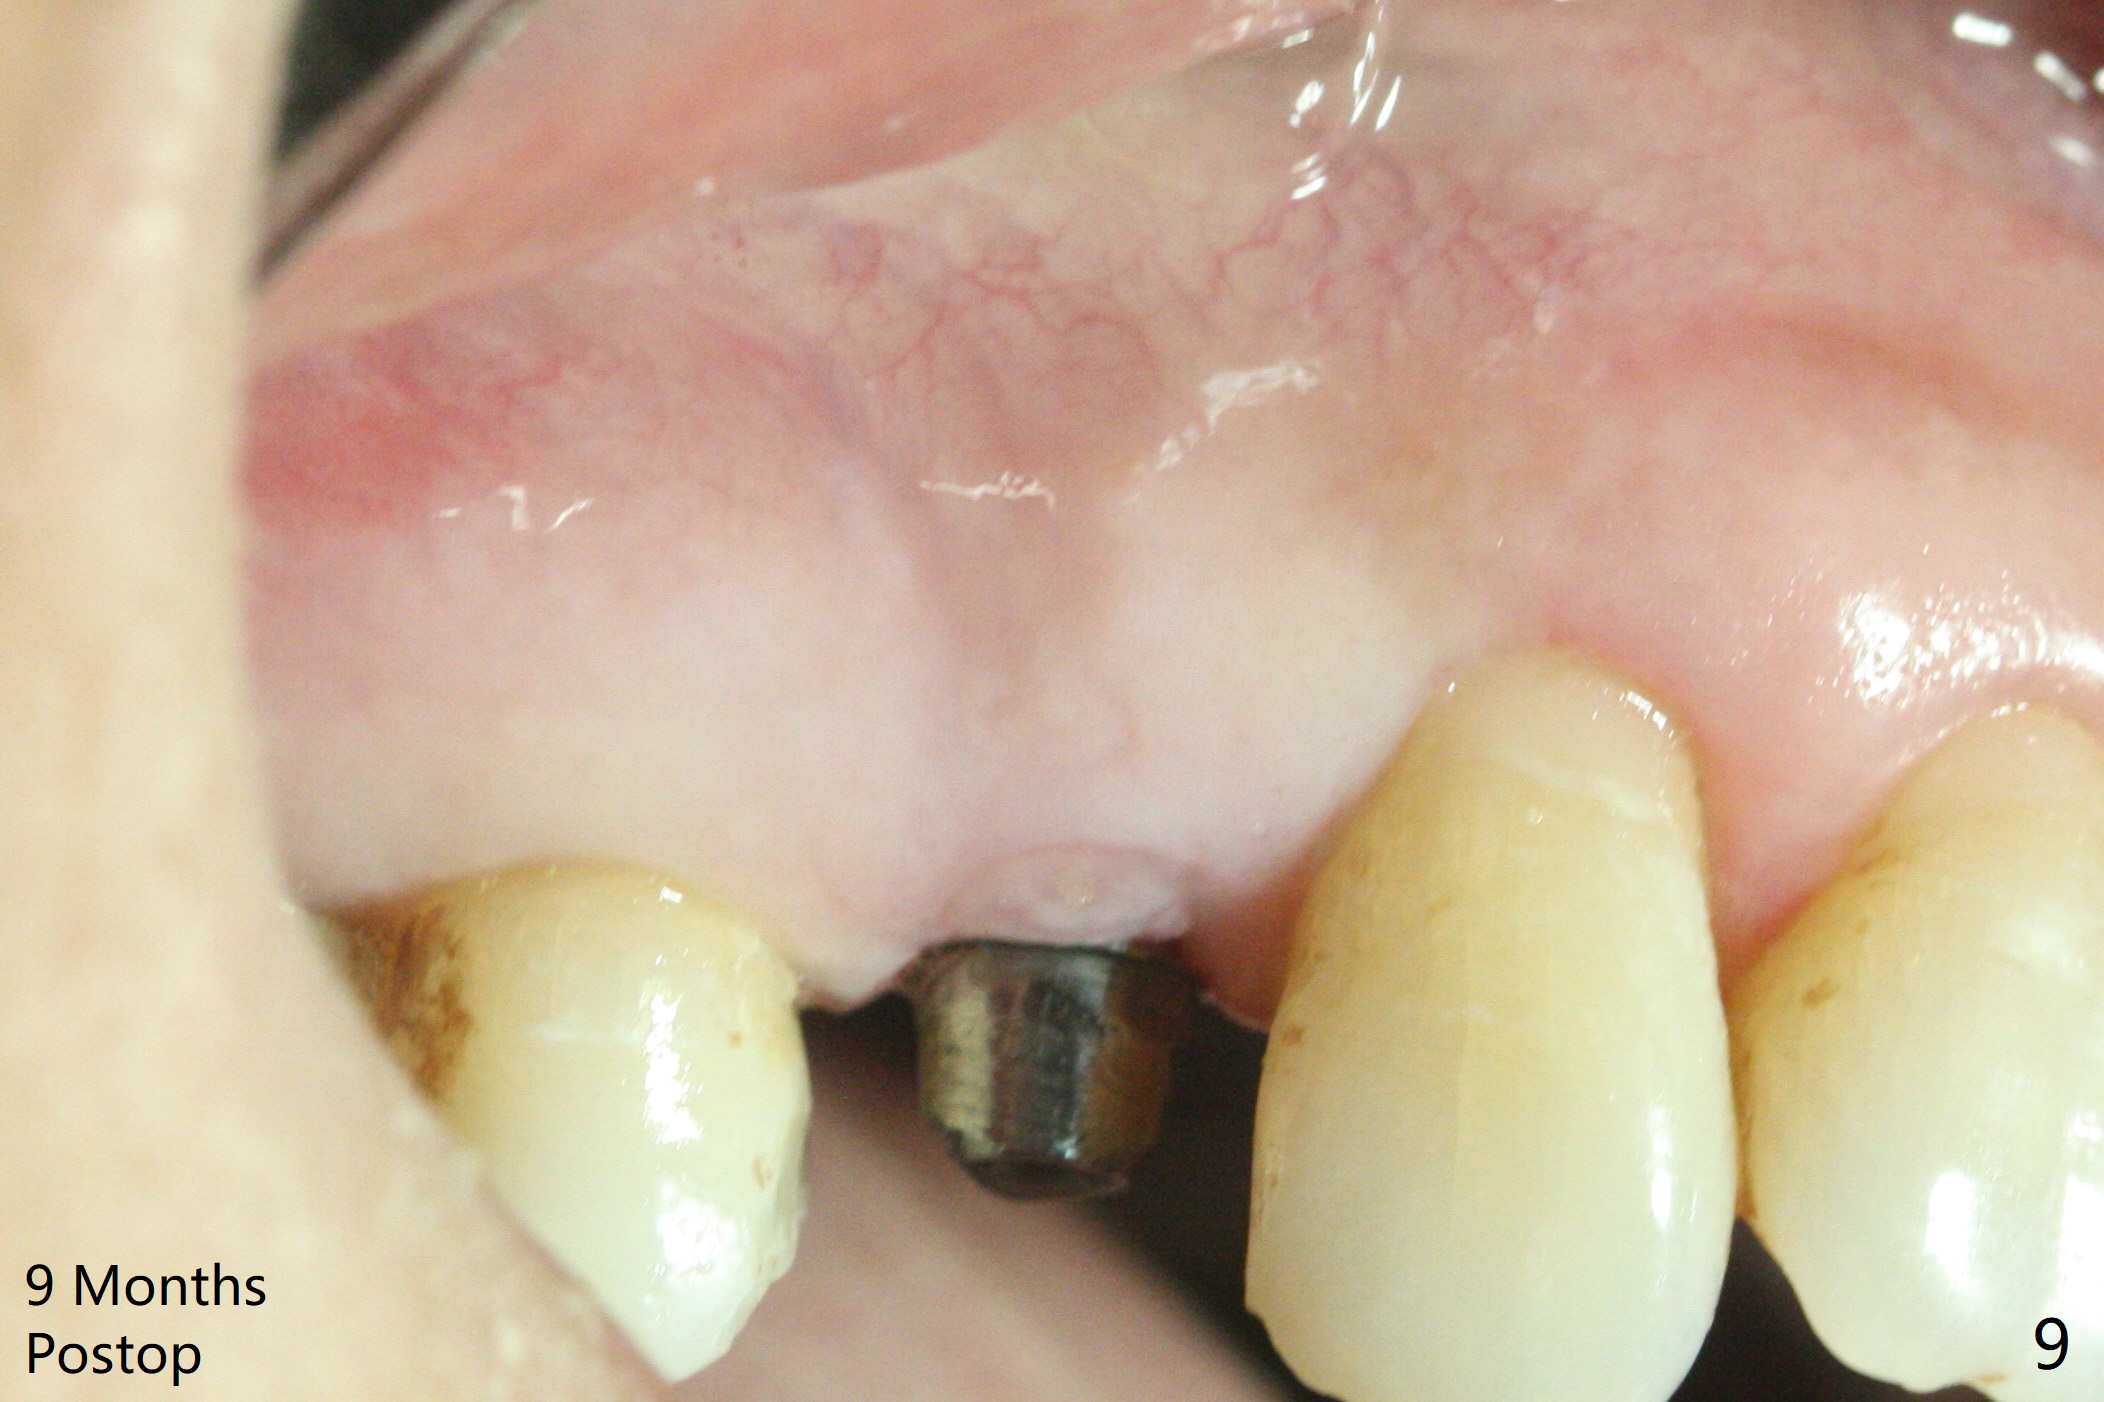

After extraction of the tooth #4 with fistula (Fig.1), the buccal bony defect is superior to the fistula. Before placement of a 4.5x17 mm tissue-level implant (Fig.2) and after osteotomy for bone-level one, PRF and mixture of autogenous bone and allograft are pushed from the socket through the buccal defect for repair (Fig.3 arrowheads). The trajectory of the implant (Fig.4) is consistent with design (Fig.5). The fistula reduces in size and in redness, while the apical elevation (as related to the underlying bone graft) remains prominent 13 days postop (Fig.6,7 *). The distal defect has been apparently repaired 9 months postop (Fig.8 *, as compared to immediately post bone graft in Fig.2). The distal defect has been apparently repaired 9 months postop (Fig.8 *, as compared to immediately post bone graft in Fig.2). The fistula disappears (Fig.9).